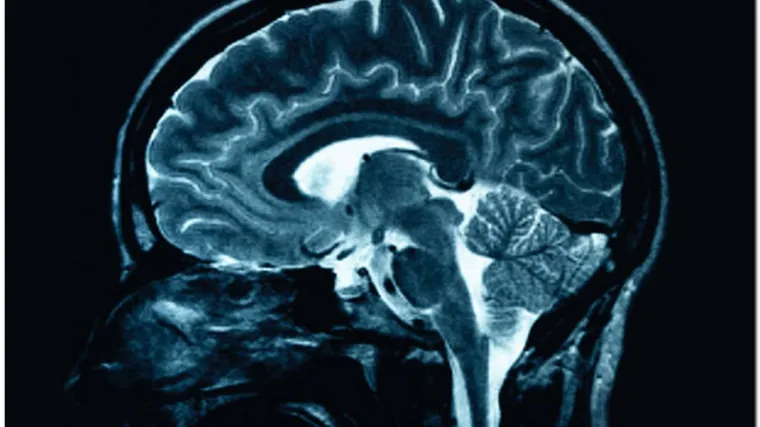

Napokon ukinute diskriminirajuće smjernice za liječenje multiple skleroze

Nakon 20 godina diskriminirajućeg liječenja više od 6000 osoba s multiplom sklerozom, od 22. studenoga u primjeni su nove smjernice HZZO-a za liječenje te kronične upalne i degenerativne bolesti središnjeg živčanog sustava koje omogućuju da oboljeli u Hrvatskoj napokon dobiju terapiju na početku bolesti, istaknuli su u srijedu iz Saveza društava multiple skleroze Hrvatske.

Uklonjena su tri diskriminirajuća kriterija za liječenje MS-a - dob do 55 godina starosti, trajanje bolesti najmanje godinu dana te dva liječena pogoršanja u dvije godine. Novost je i uvođenje lijeka za liječenje primarno progresivnog oblika multiple skleroze.

Neurologinja s KBC-a Zagreb Tereza Gabelić istaknula je da je novost, osim novih smjernica za liječenje MS-a, i mogućnost propisivanja novog lijeka pacijentima s primarno progresivnim oblikom MS-a, što do sada nije bilo moguće, niti je na listi lijekova postojao lijek za primarno progresivni oblik te bolesti.

Kazala je da je Hrvatska zemlja s visokom prevalencijom oboljelih od MS-a, te naglasila značaj ranog liječenja bolesnika.

"Osim što je ovo neprocjenjiva važnost za naše bolesnike, za državu je ovo ogromni napredak jer godinama postavljamo dijagnozu bolesti slijedeći sve svjetske smjernice. Međutim, u terapiji smo kaskali. Na ovaj način postajemo ravnopravna članica EU koja po svim najnovijim dijagnostičkim i terapijskim smjernicama liječi naše bolesnike", poručila je Gabelić.

Napomenula je kako novi kriteriji omogućuju rano liječenje bolesnika, kojim odmah po postavljenoj dijagnozi bolesti mogu započeti imunomodulacijsko liječenje, čime se i na dugi niz godina može djelovati na neurološke ishode bolesnika te spriječiti nastajanje nesposobnosti, odnosno invalidnosti.

Gabelić je kazala i da su sve studije pokazale da se primjenom prve linije liječenja na period od 15 do 20 godina za 50 posto smanjuje nastajanje invalidnosti bolesnika.